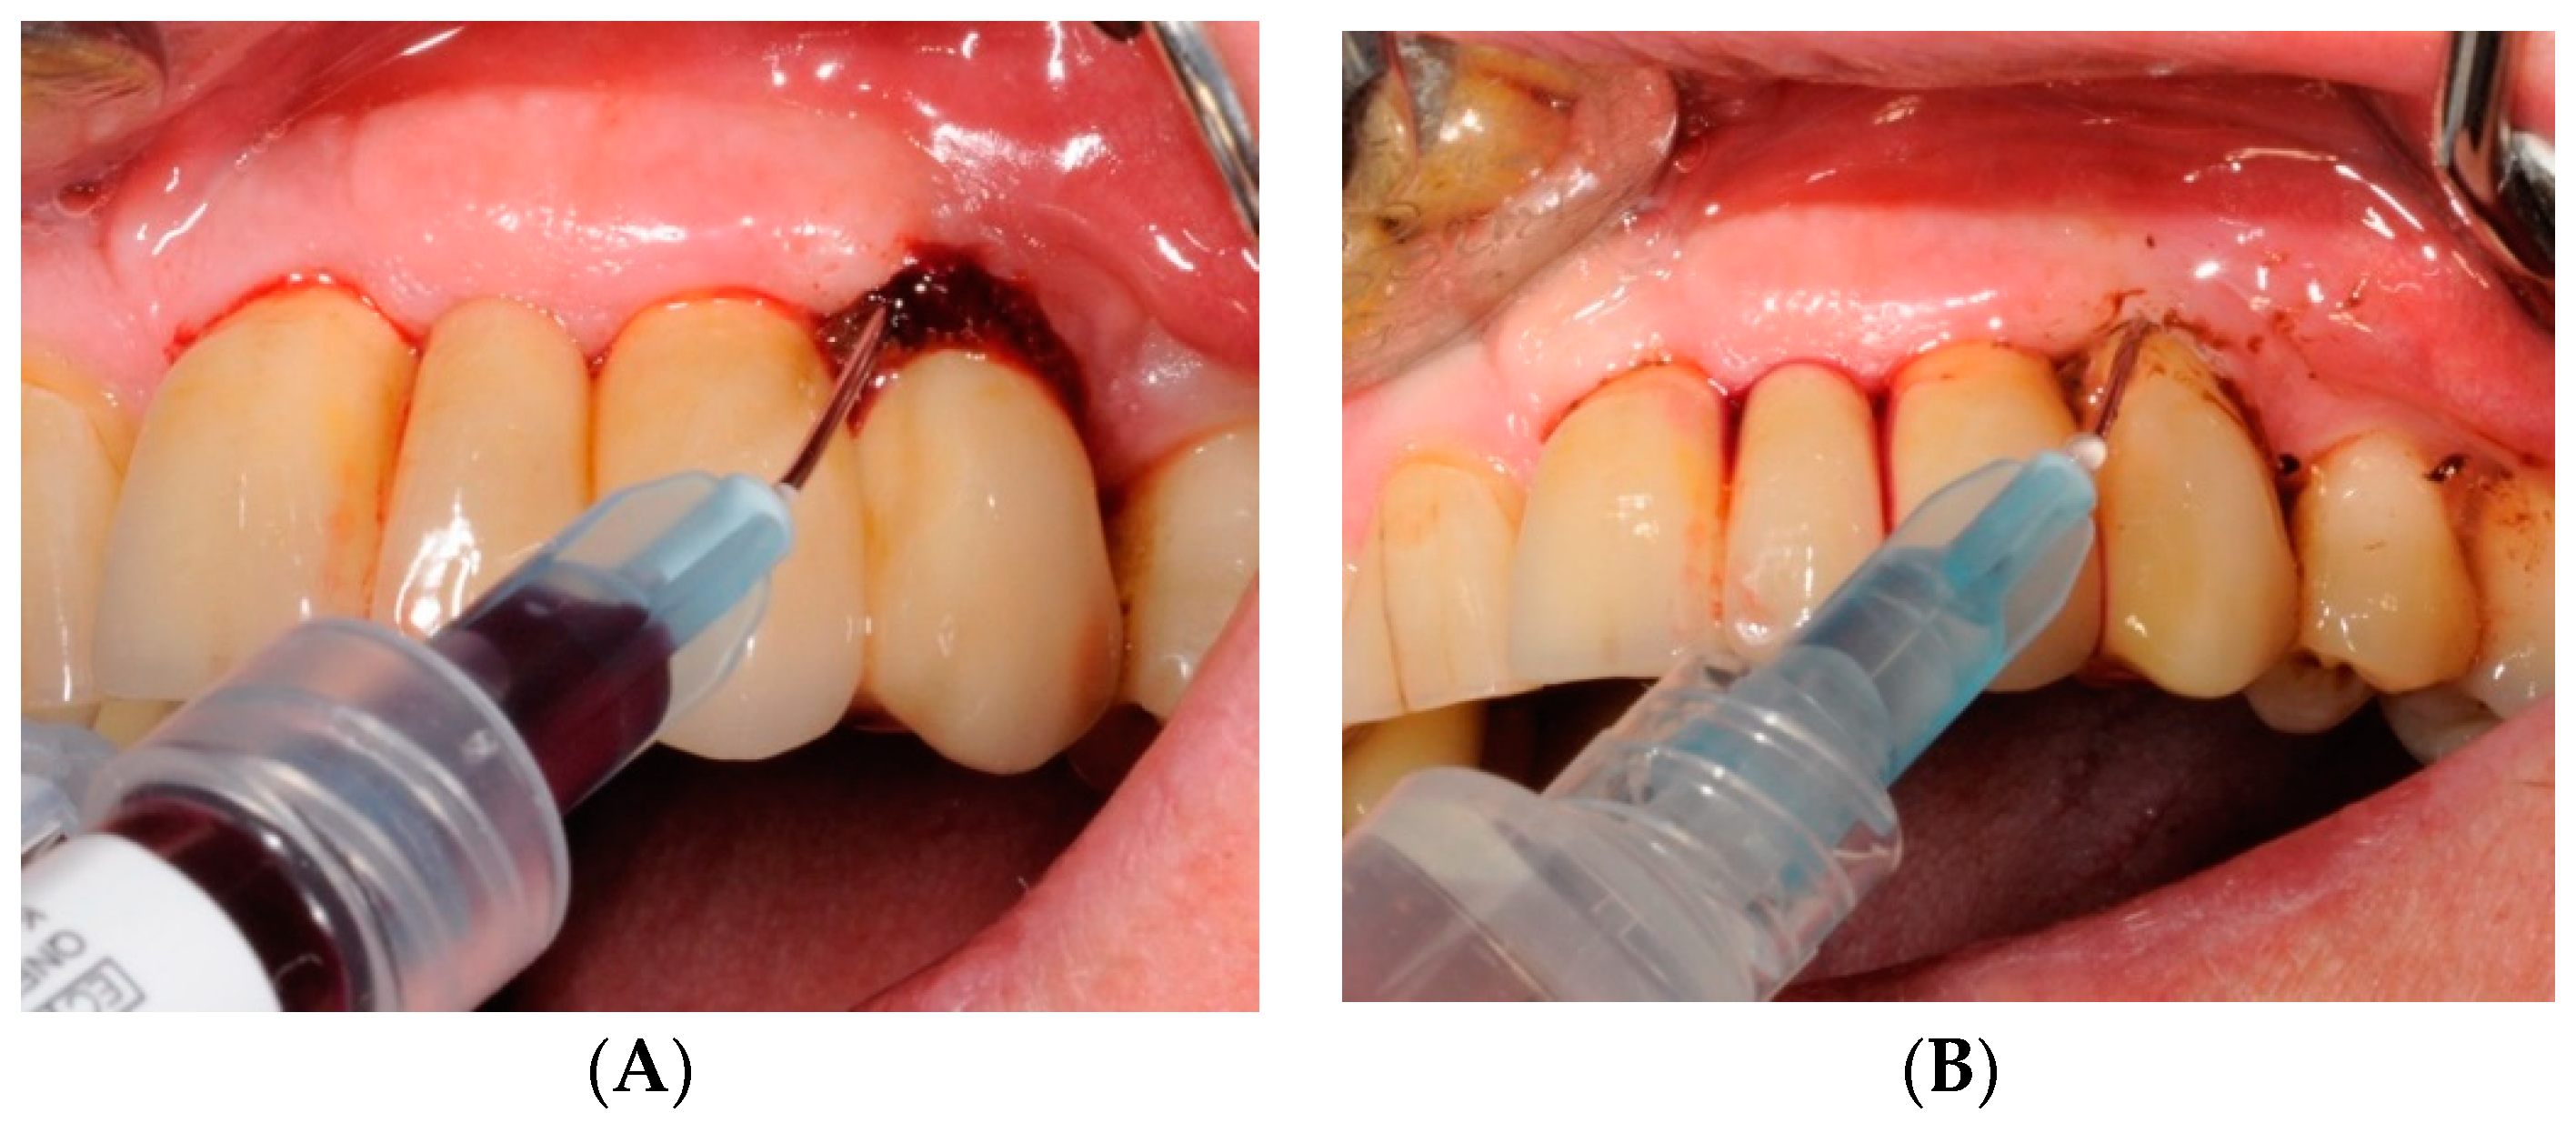

4.5. Test Substances and Administration

4.6. Patients’ Degree of Satisfaction